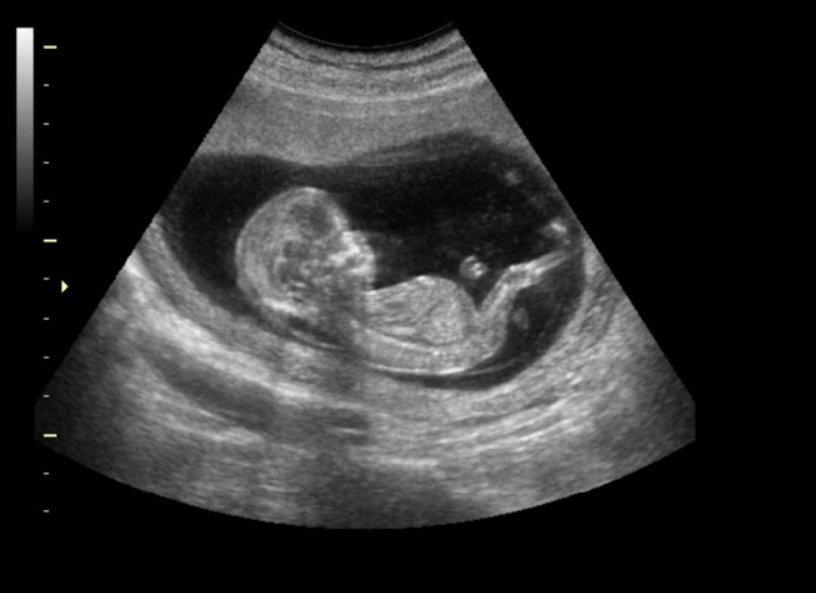

Este tipo de ecografía se puede realizar en cualquier semana del embarazo. Si bien las mejores imágenes se obtienen entre la semanas 26 y 29, si no se quiere esperar tanto, se puede hacer a partir de la semana 17, momento en el que se puede identificar correctamente el sexo del bebé.

Quizá sea la ecografía más importante del embarazo. Con operadores experimentados y con el equipamiento adecuado podemos detectar la mayoría de las malformaciones fetales diagnosticadas en la vida prenatal. Se realizan también los riesgos de preeclampsia.

• Scan fetal (Ecoanatomía Fetal / Scan Morfológico Fetal / Scan Detallado)